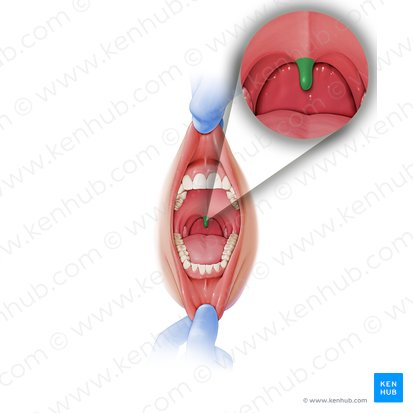

Uvula

Lingual frenulum

Openings of submandibular ducts